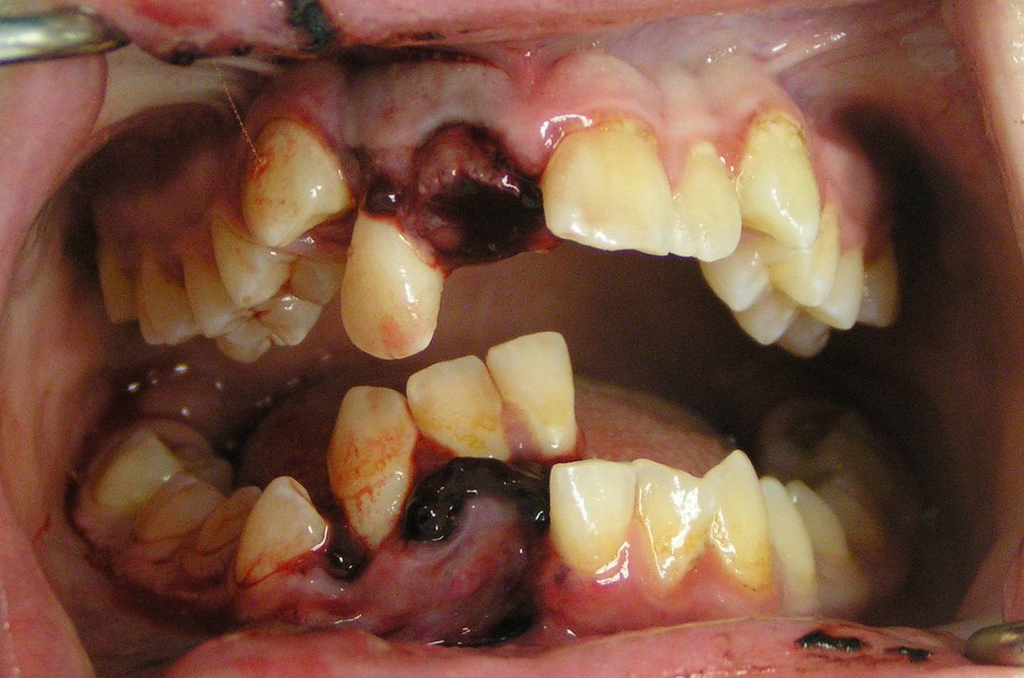

In this sense, trauma to teeth and their supporting tissues. This involves injuries to the dental hard tissues (enamel, dentine and cement), the pulp and the alveolar process, to concussion of the tooth to avulsion of the tooth and its re-implacement within its socket.